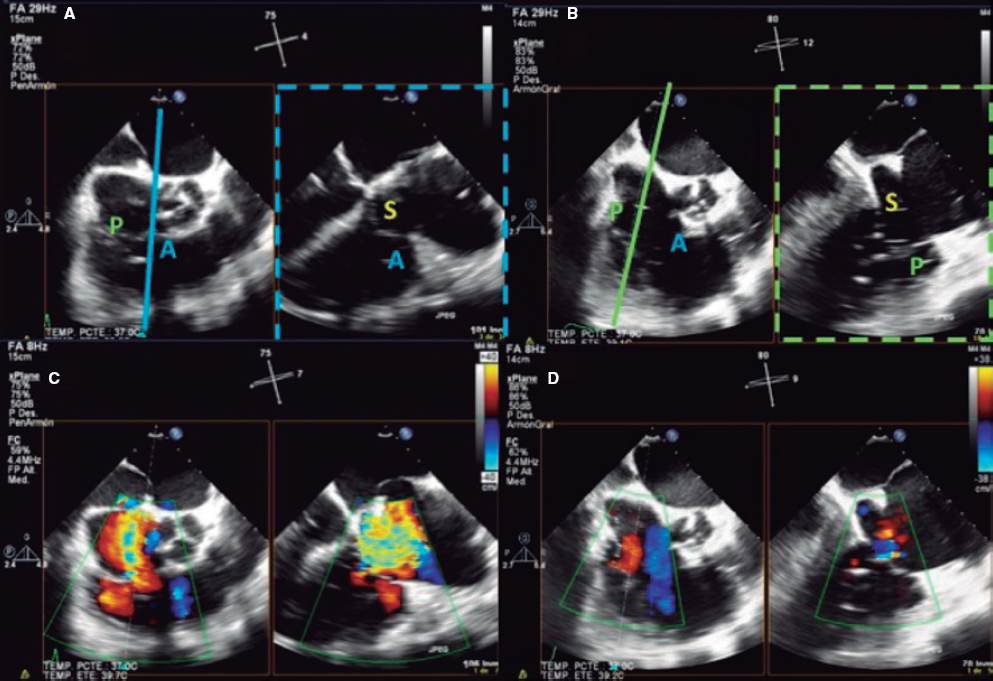

2. Mid-esophageal view of the RV inflow and outflow tract (intercommissural tricuspid view) between 60° and 90°. It shows the imaginary line from the anteroseptal (A-S) commissure up to the posteroseptal (P-S) commissure. The anterior leaflet close to the aorta and the posterior leaflet on the lateral side can be seen (video 1 of the supplementary data). This is the reference view to obtain biplanar images for the assessment of the septal leaflet. By bringing the cursor close to the aorta (X-plane tool), the orthogonal view shows the A-S coaptation and the anterior and septal leaflets. By moving it away from the aorta towards the lateral position, the view shows the P-S coaptation and the posterior and septal leaflets. The same views should be acquired using the Doppler color technique (figure 2) to see whether the origin of the regurgitant jet is of anterolateral or P-S predominance.

Figure 2. Intercommissural mid-esophageal view. A: when placing the cursor next to the aorta, the orthogonal view shows the anteroseptal coaptation line. B: by moving the cursor towards the most lateral region, the orthogonal view is acquired showing the posteroseptal coaptation line. C and D: color biplanar imaging showing the origin of regurgitation jet. A, anterior; P, posterior; S, septal.

Also, these views are useful to measure the length of the leaflets, see coaptation defects, assess the movement of the leaflets, and see the presence of strings that can make the procedure difficult. The presence of serious restrictions in the movement of the septal leaflet limits the performance of the procedure with the current device.